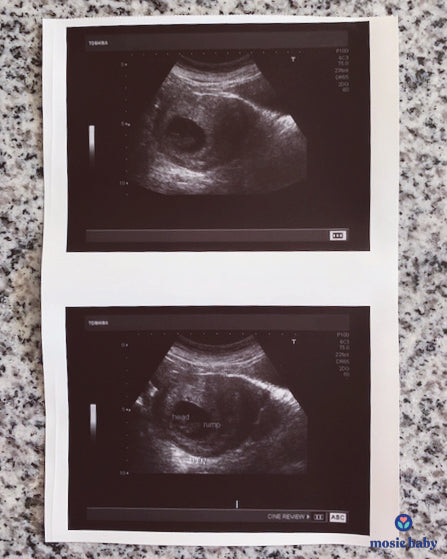

Here is a picture of our first sonogram! So grateful to Mosie baby!!!